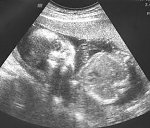

Tirli gratulację a Zosieńka niech rośnie zdrowo w brzusiu.

Tirli GRATULUJE ZDROWEJ CORECZKI

Tirli no pieknie kolejna królewna i jaka ładniutka